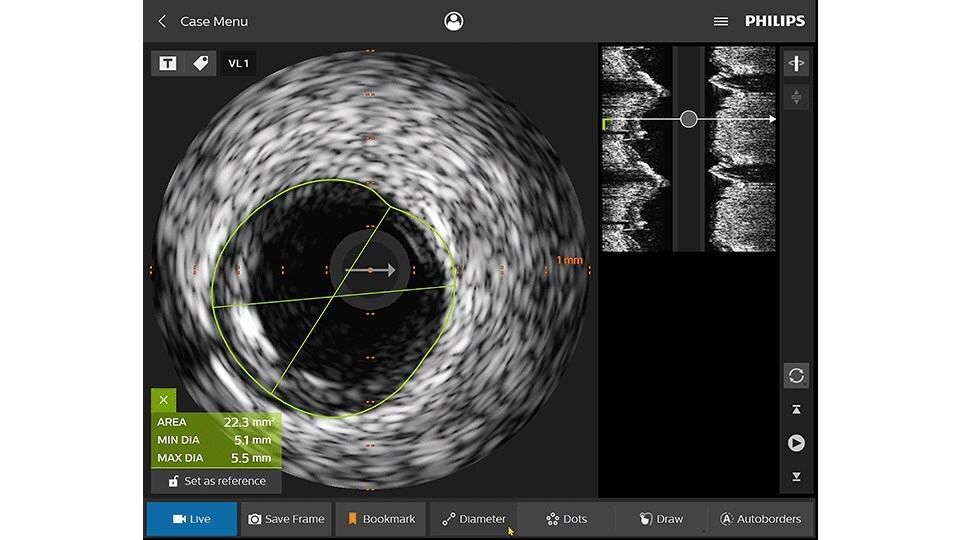

Intravascular ultrasound (IVUS) provides images from within the vessel to accurately assess and optimize your treatment plan.